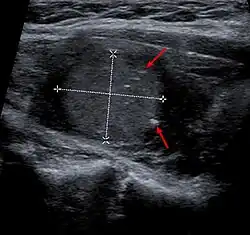

Medullary thyroid carcinoma on ultrasound with typical small calcifications (arrows)

Diagnosis is primarily performed via fine needle aspiration of the lesion of the thyroid to distinguish it from other types of thyroid lesions.[7] Microscopic examination will show an amyloid stroma with hyperplasia of parafollicular cells.